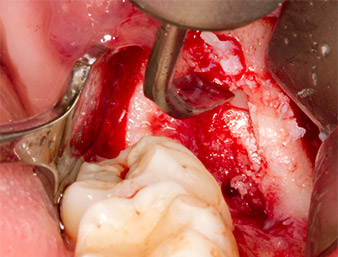

Piezomed S2

Fig. 6: Il residuo di radice viene esposto con attenzione con uno strumento sferico ricoperto in diamante (Piezomed S2) e i bordi dell'osso sono levigati.

residuo di radice 38

Fig. 7: Il residuo di radice 38 (LL8) è ben esposto nel suo alveolo per la successiva rimozione.

Per esporre il residuo di radice con il minor trauma possibile al tessuto, è stato utilizzato un ulteriore strumento (Piezomed S2) indicato principalmente per la preparazione della finestra laterale nel rialzo del seno mascellare. Inoltre, è stata usata una sfera ricoperta in diamante per levigare i bordi affilati dell'osso (Fig. 6 e 7). Tutti gli accessori Piezomed sono stati usati con l'impostazione automatica predefinita adatta senza funzione di potenziamento.